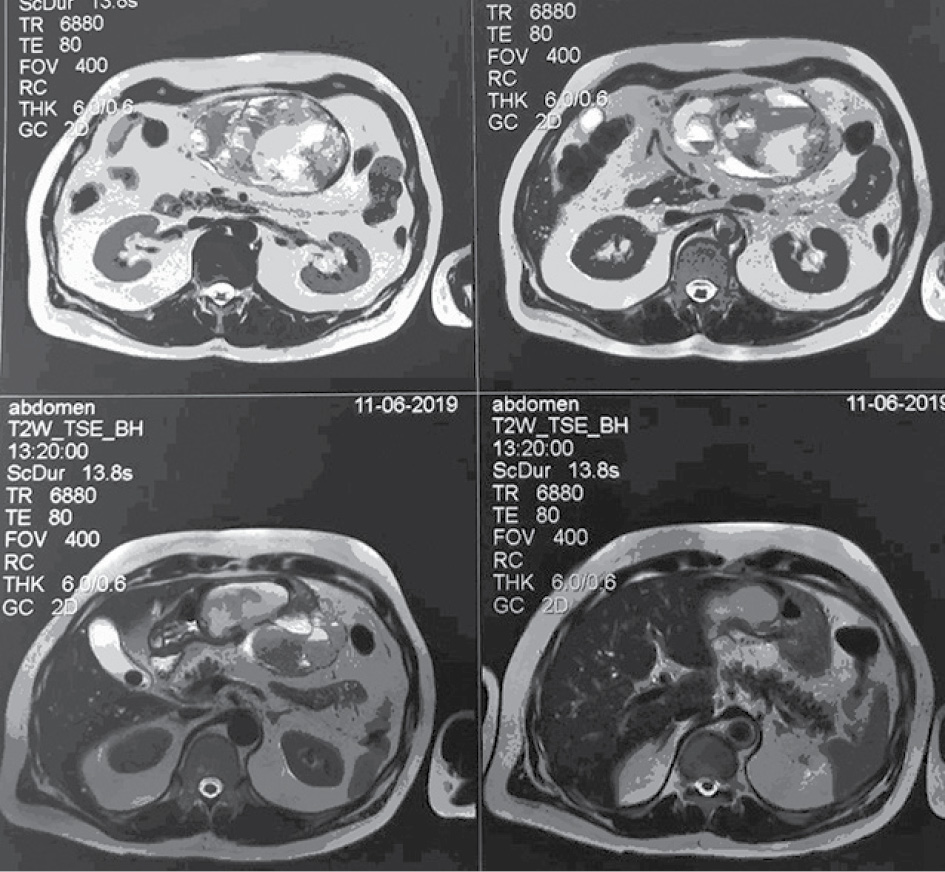

- МРТ с контрастированием от 11.06.2019 г. Заключение: Объёмное образование брюшной полости слева, кистозно-солидной структуры со сдавлением желудка (tumor). Множественные кисты обеих долей печени. Конкремент желчного пузыря. Увеличенные забрюшинные лимфатические узлы (рис. 1–4).

Рис. 1. Увеличенные забрюшинные лимфатические узлы

Рис. 2. Увеличенные забрюшинные лимфатические узлы

Рис. 3. Увеличенные забрюшинные лимфатические узлы

Рис. 4. Увеличенные забрюшинные лимфатические узлы